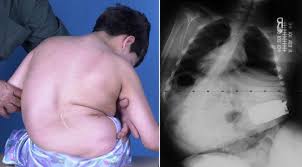

اعوجاج العمود الفقري العصبي العضلي هو أحد أنواع الاعوجاج الثلاثة الرئيسية، ويحدث نتيجة اضطرابات تؤثر على الأعصاب أو العضلات، مثل الشلل الدماغي، السنسنة المشقوقة، أو إصابات الحبل الشوكي. عندما تصبح العضلات ضعيفة أو متشنجة أو مشلولة، لا تستطيع دعم العمود الفقري بشكل صحيح، مما يؤدي إلى انحنائه أثناء نمو الطفل.

عادةً تظهر العلامات مبكرًا في حياة الطفل، ويمكن للأهل أو الطبيب ملاحظتها بسهولة. أبرز هذه الأعراض تشمل:

ميل أو وضعية غير متوازنة عند الجلوس.

الاعتماد على الذراعين لدعم الجسم أثناء الجلوس.

اختلاف ارتفاع الكتفين أو الوركين.

ميلان الرأس عن مركز الجسم.

بروز غير متساوٍ لعظام الكتفين.

تدلي الذراعين بشكل غير متماثل.